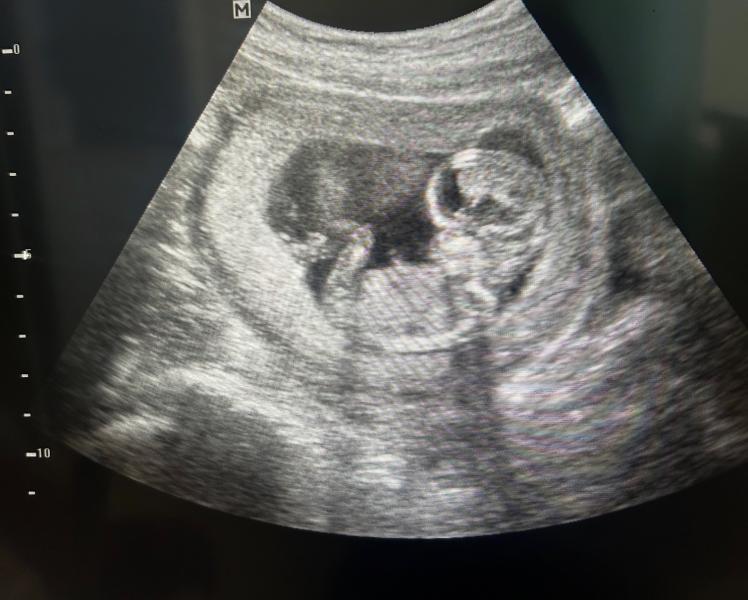

Положил ногу на ногу и лежит, ждёт чего-то важного.

Пол пока не знаем, и видимо не узнаем, раз такой расклад😂👌🏼

Как будто ещё такой: пу-пу-пууу....сколько дееел

Еще бы руки за голову и вообще забавно было бы 🤭 как на диване 😃